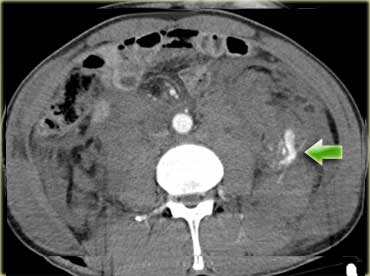

Các dấu hiệu bao gồm:

- Giảm tưới máu lách (mũi tên vàng).

- Nhiều vùng thoát thuốc cản quang (mũi tên xanh lá).

- Tràu máu ổ bụng và tràn khí ổ bụng.

- Nhiều đoạn ruột có thành dày lan tỏa (mũi tên xanh dương).